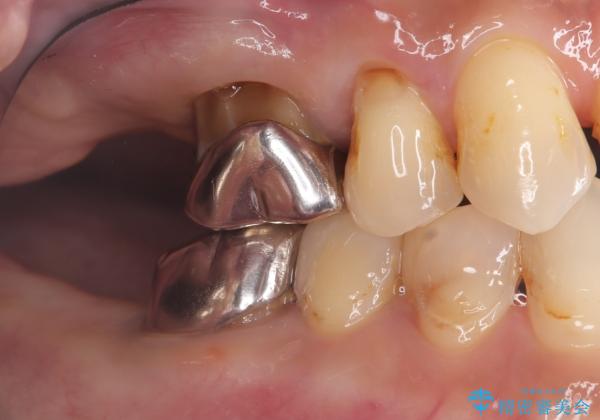

まず、右上6・右下6の根管治療を再度行い、根の状態をしっかり整えた上で、セラミッククラウンを装着しました。さらに、欠損していた右上7・右下7にはインプラントを埋入し、セラミッククラウンを装着。治療後は、「奥歯でしっかり噛めるようになり、不安なく食事ができるようになった」と患者様にも大変ご満足いただきました。